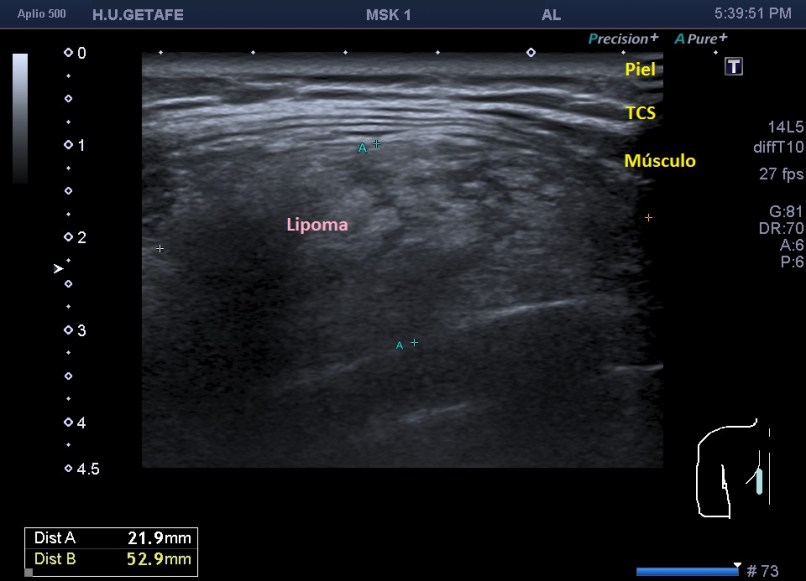

Cuando hacemos un recorrido sobre la lesión descubrimos que tiene casi 11 centímetros de eje largo. Al contrario de la imagen del caso anterior, vemos una imagen enorme, hipoecogénica o isoecogénica junto con la grasa del tejido celular subcutáneo, que puedes ver en este detalle anatomoecográfico:

La imagen marca la línea amarilla que es la fascia de separación entre el músculo y el tejido celular subcutáneo que me vale para enlazar con otro gran aspecto a tener en cuenta en el estudio de los lipomas, que es su situación. Cuando tenemos un lipoma es super importante saber si es subcutáneo o es intramuscular por que el manejo terapéutico y para eso quiero que te fijes en la imagen superior, si miras la línea amarilla, está marcando la separación entre TCS y Musculatura.

Si el lipoma está en el tejido celular subcutáneo estará por encima de esta línea amarilla, si es intramuscular, estará por debajo, de este modo debemos reconocer siempre las distintas semiologías del tejido superficial y estar muy pendientes de las fascias entre el tejido celular subcutáneo y el muscular, fácil de discernir, por otro lado en la mayoría de las ocasiones.